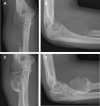

We provide an overview of imaging, histopathology, genetics, and multidisciplinary treatment of giant cell tumor of bone (GCTB), an intermediate, locally aggressive but rarely metastasizing tumor. Overexpression of receptor activator of nuclear factor κB ligand (RANKL) by mononuclear neoplastic stromal cells promotes recruitment of numerous reactive multinucleated giant cells. Conventional radiographs show a typical eccentric lytic lesion, mostly located in the meta-epiphyseal area of long bones. GCTB may also arise in the axial skeleton and very occasionally in the small bones of hands and feet. Magnetic resonance imaging is necessary to evaluate the extent of GCTB within bone and surrounding soft tissues to plan a surgical approach. Curettage with local adjuvants is the preferred treatment. Recurrence rates after curettage with phenol and polymethylmethacrylate (PMMA; 8%-27%) or cryosurgery and PMMA (0%-20%) are comparable. Resection is indicated when joint salvage is not feasible (e.g., intra-articular fracture with soft tissue component). Denosumab (RANKL inhibitor) blocks and bisphosphonates inhibit GCTB-derived osteoclast resorption. With bisphosphonates, stabilization of local and metastatic disease has been reported, although level of evidence was low. Denosumab has been studied to a larger extent and seems to be effective in facilitating intralesional surgery after therapy. Denosumab was recently registered for unresectable disease. Moderate-dose radiotherapy (40-55 Gy) is restricted to rare cases in which surgery would lead to unacceptable morbidity and RANKL inhibitors are contraindicated or unavailable.